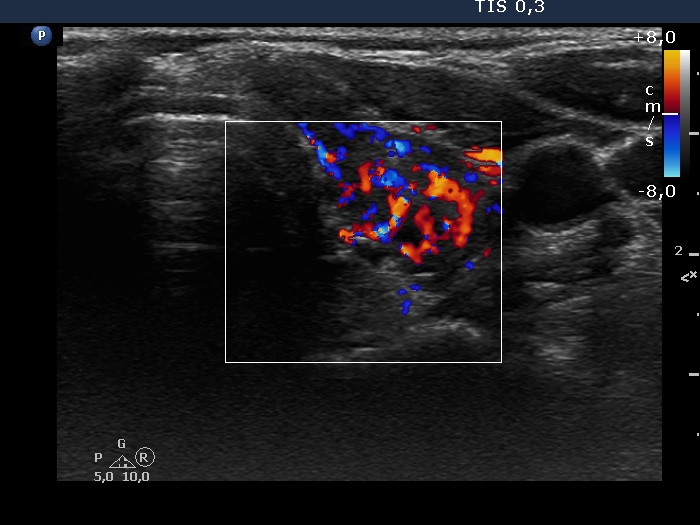

Consecutive patients with Hashimoto's thyroiditis - Case 10. (ultrasonographic picture 7)

Left lobe, horizontal scan, color Doppler mode. The vascularization is extremely increased.